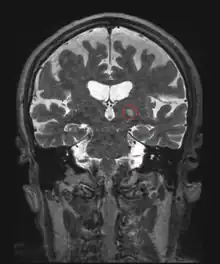

In terms of pathophysiology, clinical, physiological and imaging studies point to an involvement of the cerebellum and/or cerebellothalamocortical circuits.[25] Changes in the cerebellum could also be mediated by alcoholic beverage consumption. Purkinje cells are especially susceptible to ethanol excitotoxicity.[26] Impairment of Purkinje synapses is a component of cerebellar degradation that could underlie essential tremor.[26] Some cases have Lewy bodies in the locus ceruleus.[27][28][29] ET cases that progress to Parkinson's disease are less likely to have had cerebellar problems.[30] Recent neuroimaging studies[31] have suggested that the efficiency of the overall brain functional network in ET is disrupted.